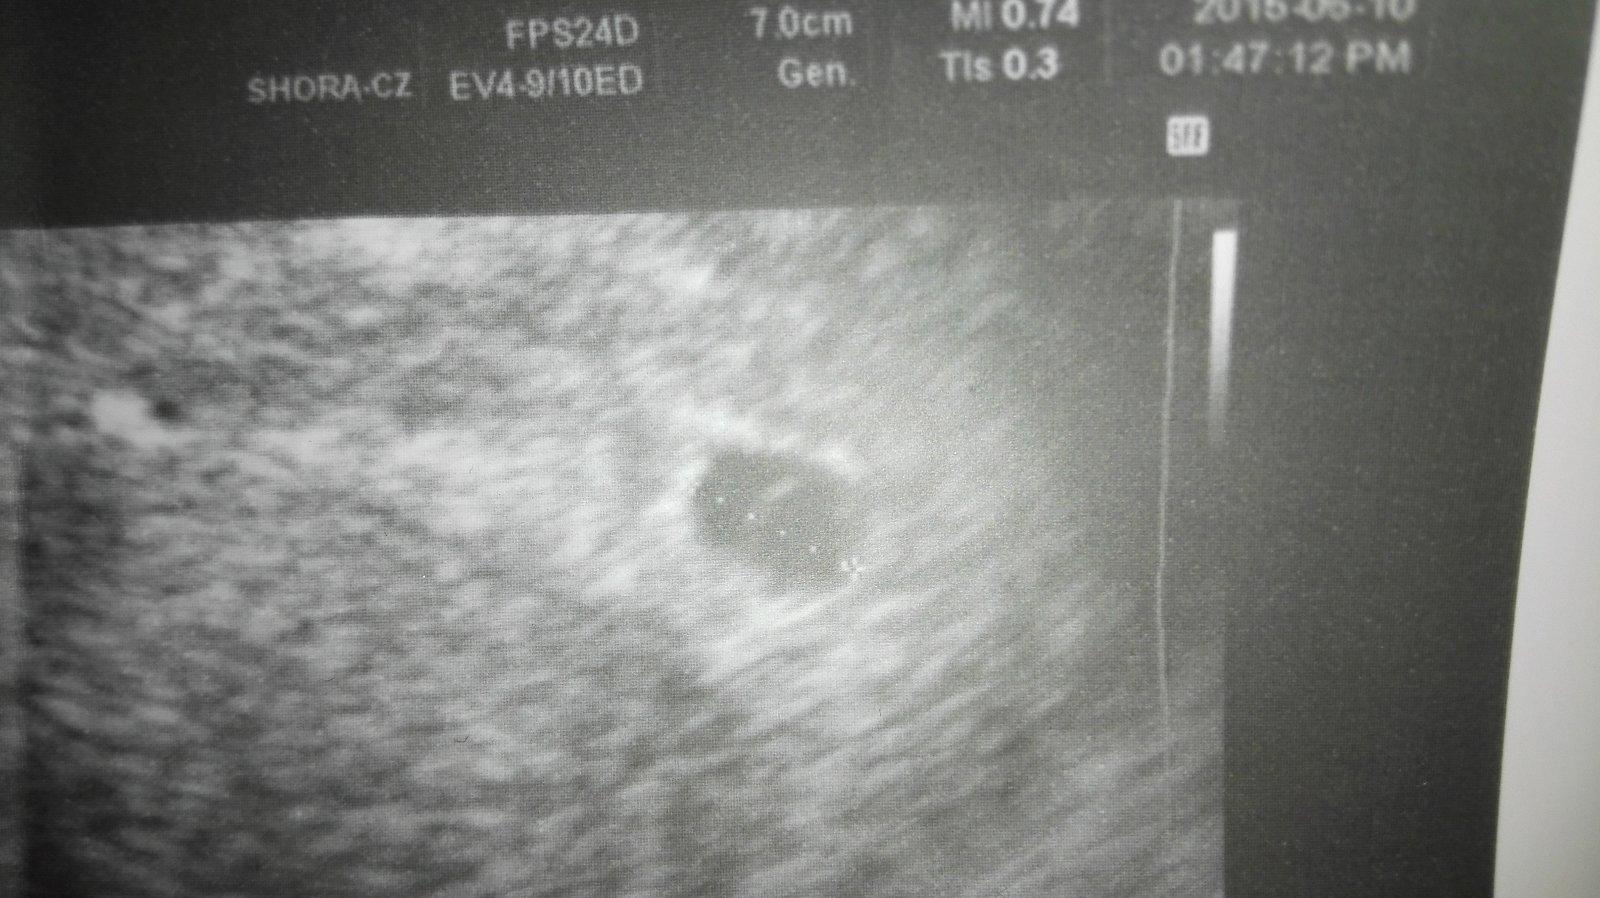

Můj gynekolog mě už od min týdne středy posílá ležet do nemocnice v pondělí sem u něho byla na kontrole a , že nevidí plod a srdíčko a že mám jít na krev hcg tak v pondělí mi jeden doktor na gynekologii říkal , že nevidí důvod at ležím tady , že mi nic není a je to mezi 5- 6 tt ve středu , že to roste , tak jak má zatím byl , tam jiný doktor. Dnes jsem šla znova do nemocnice a byl tam zrovna můj gynekolog a jsem z toho v šoku mi řekl , že je to nejspíš mimoděložní , že prostě zatím sme bez plodu a že mám další gest vaček vedle vaječniku, a mám hcg něco přes 5000 málo to šlo nahoru nešlo to ani jednou tolik . Tak sem se ho ptala co mám dělat a on ,že mám být v nemocnici , že otazka času kdy mi to praskne a vykrvácím a že příjdu o vaječník , tak se ptám , jestli teda jestli sem těhotná a on , že jo ale že neví kde a že příjdu nejspíš o vaječník. No a tak sem se rozbrečela a šla k jinému doktorovi ten mi řekl že gest,váček je v děloze 100% a že mimo děložní to není a může to bát cysta , která zasobuje těhot.nebo co , že prostě může zmizet - 100 krát sem se zeptala , že jestli to je v děloze a on že joo , že se ještě nestalo aby byl gest vaček tam i tam . A pokud mě něco bude bolet hodně , na pravo že mám letet do nemocnice , ale zatím nevidí důvod. Jsem v šoku prostě a , že pokud se to nebude vyvíjet , že prostě bud to samo potratí nebo výškrab nic víc .

Ale je mi nejak nevolno mam novou foto myslim kdyby bylo krvsceni videl by to na utz doufam. Musime pockat dokud nebude srdicko 🙂